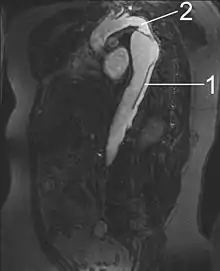

An arterial dissection is a tear within the wall of an artery, which allows blood to separate the wall layers. There are several types. Usually, a tear is in an arterial wall, but a vein wall tear has been documented.[1]

By separating a portion of the wall of the artery (a layer of the tunica media or in some cases tunica intima), a tear creates two lumens or passages within the vessel, the original or true lumen, and the false lumen created by the new space within the wall of the artery. It is not yet clear if the tear in the innermost layer, the tunica intima, is secondary to the tear in the tunica media. Dissections originating in the tunica media are caused by disruption of the vasa vasorum. It is thought that dysfunction in the vasa vasorum is an underlying cause of dissections.[2]